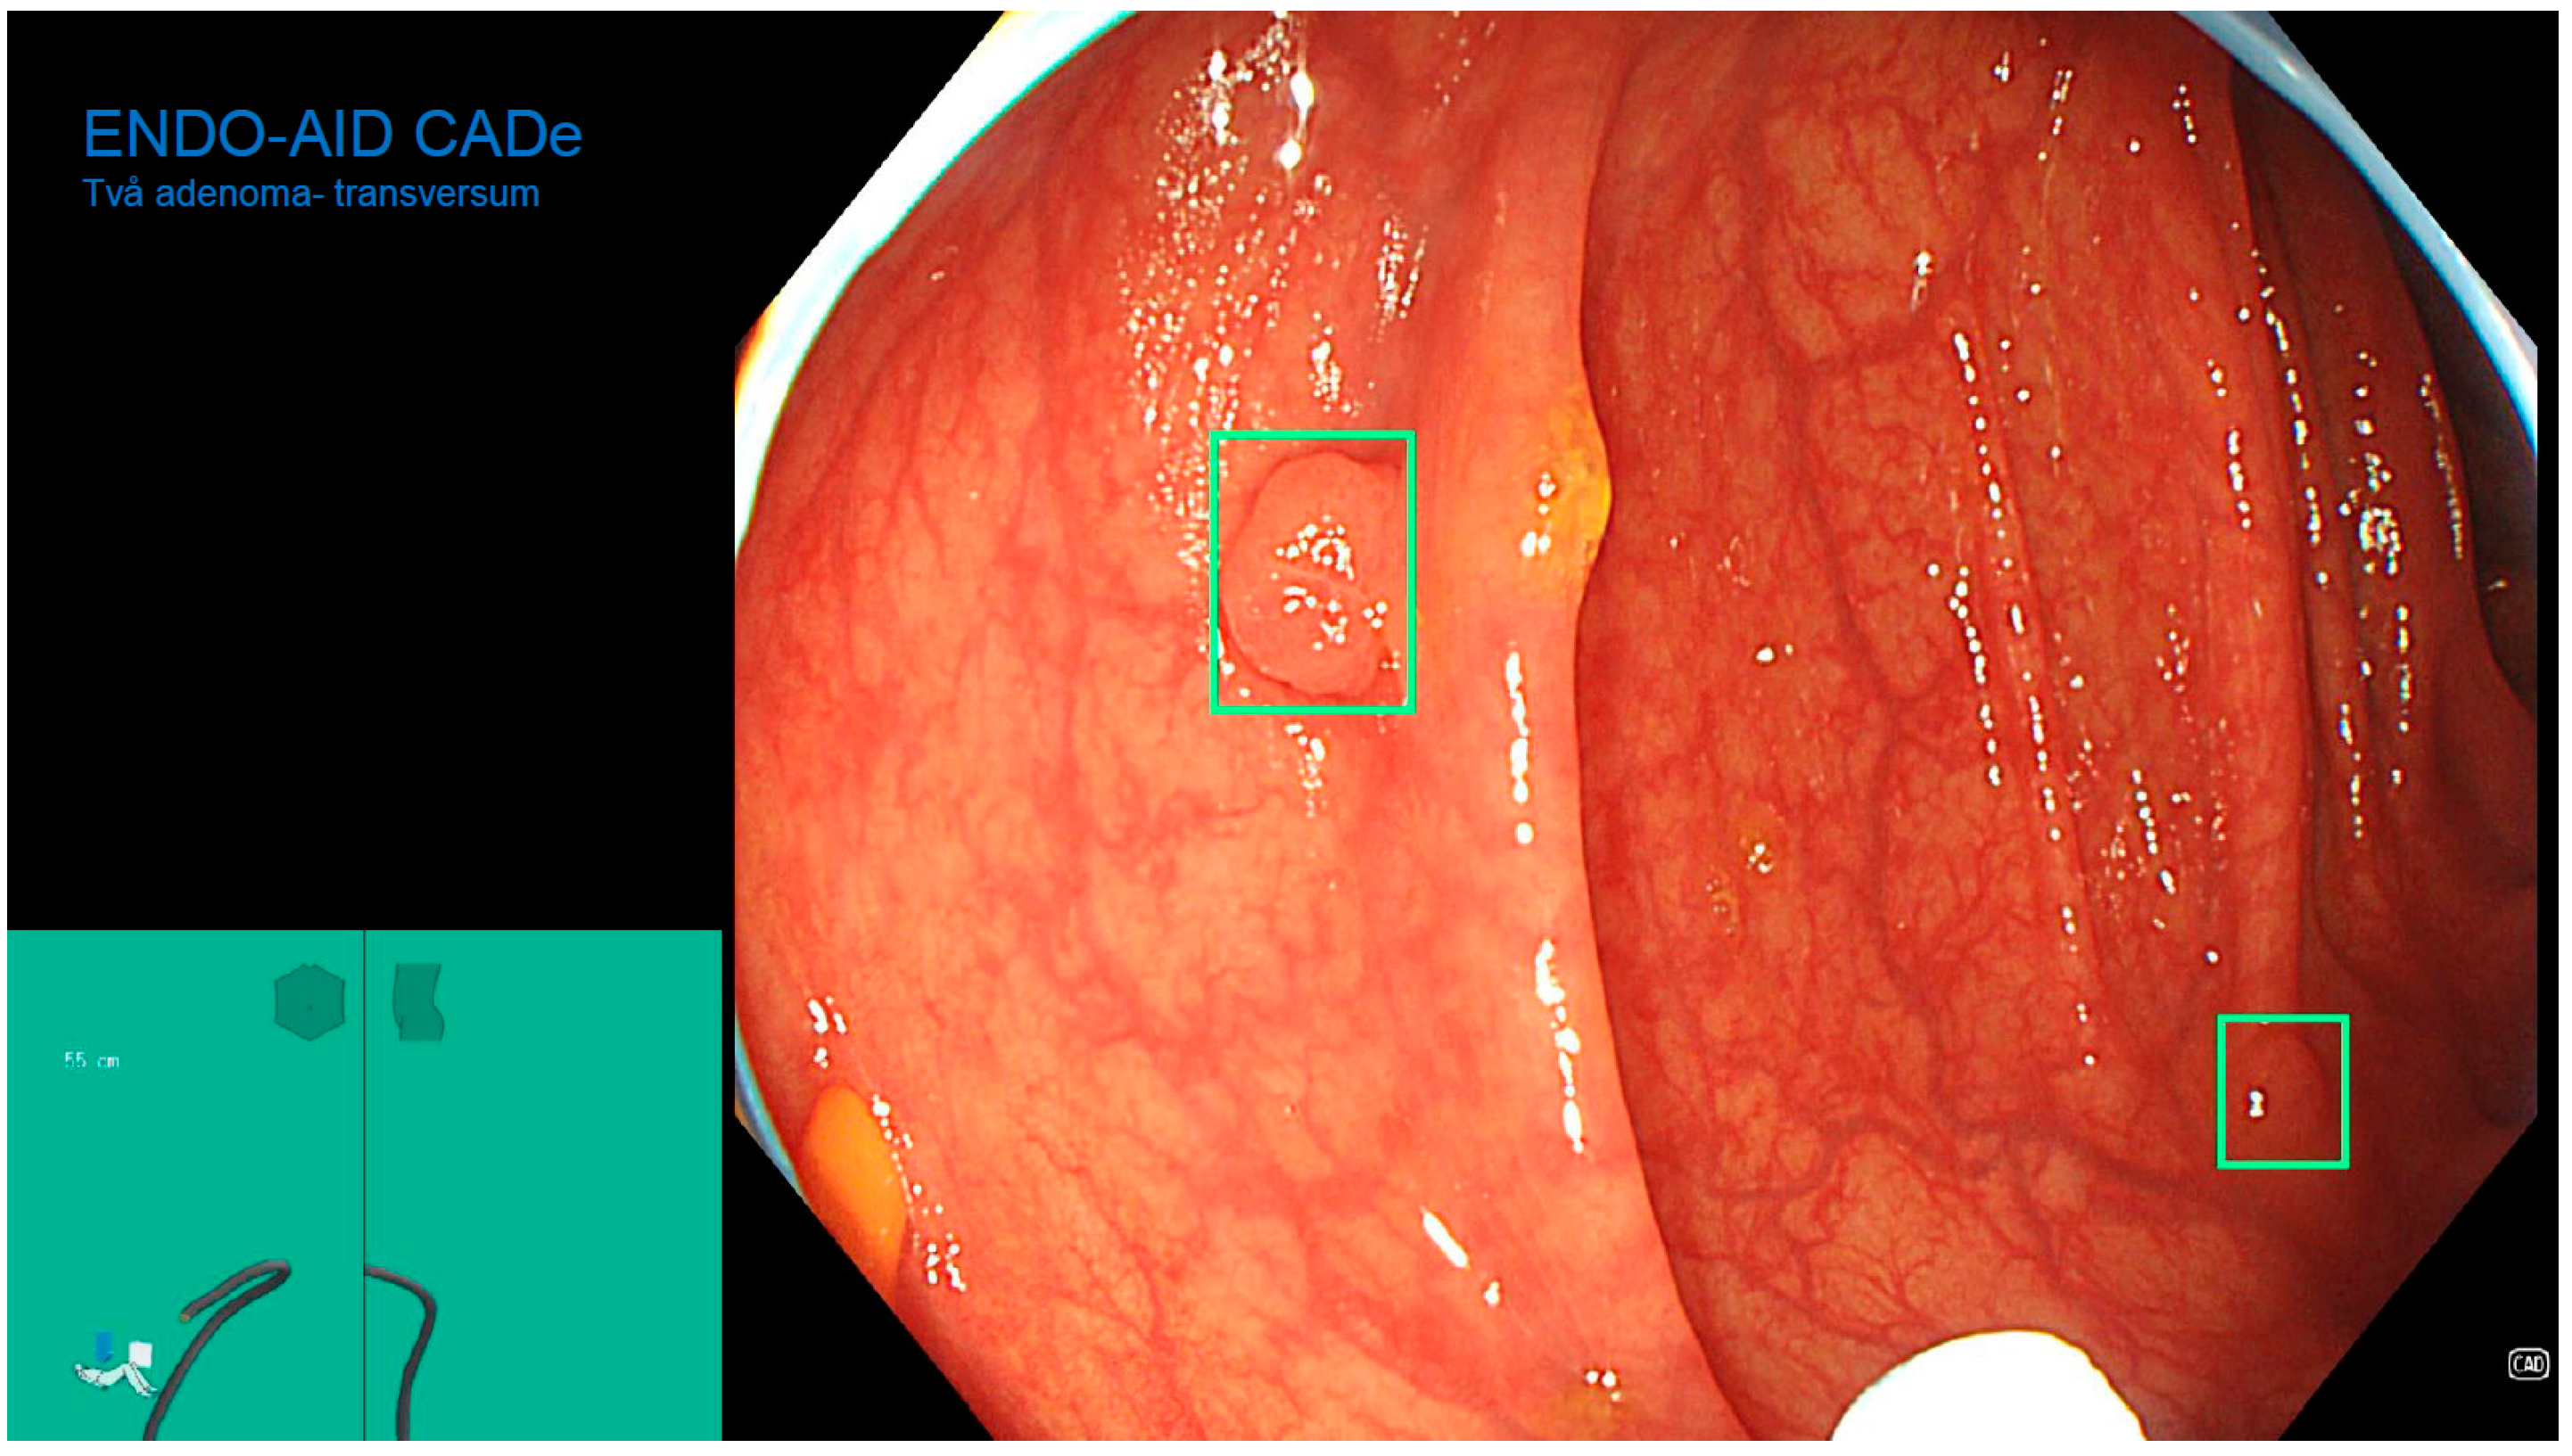

The Role of an Artificial Intelligence Method of Improving the Diagnosis of Neoplasms by Colonoscopy

The Role of Artificial Intelligence in Colonoscopy Examinations